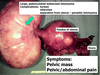

Q

Name 3 unusual sites of endometriosis

A